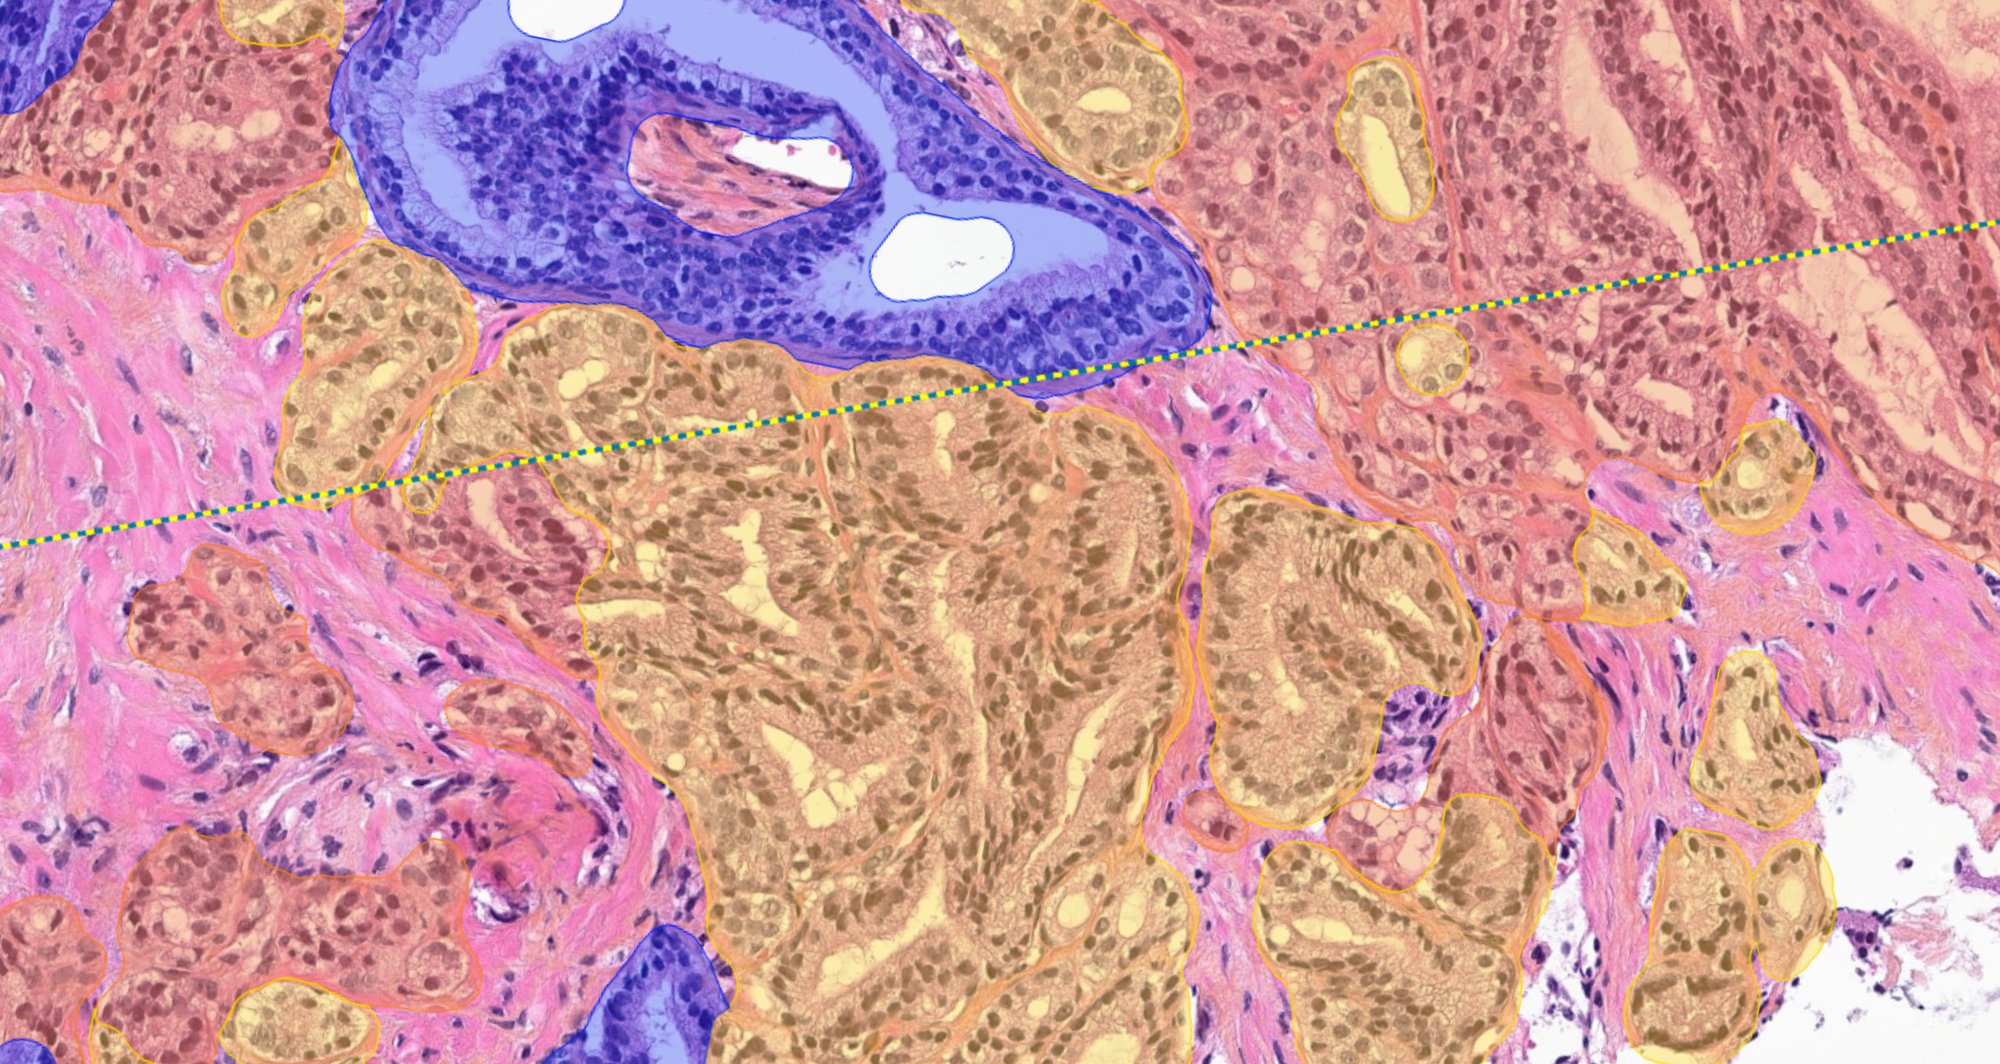

Aiforia® Prostate Cancer Suite consists of AI models with an optimized interactive user interface that supports pathologists in Gleason grade grouping and identifying adverse histopathological features.